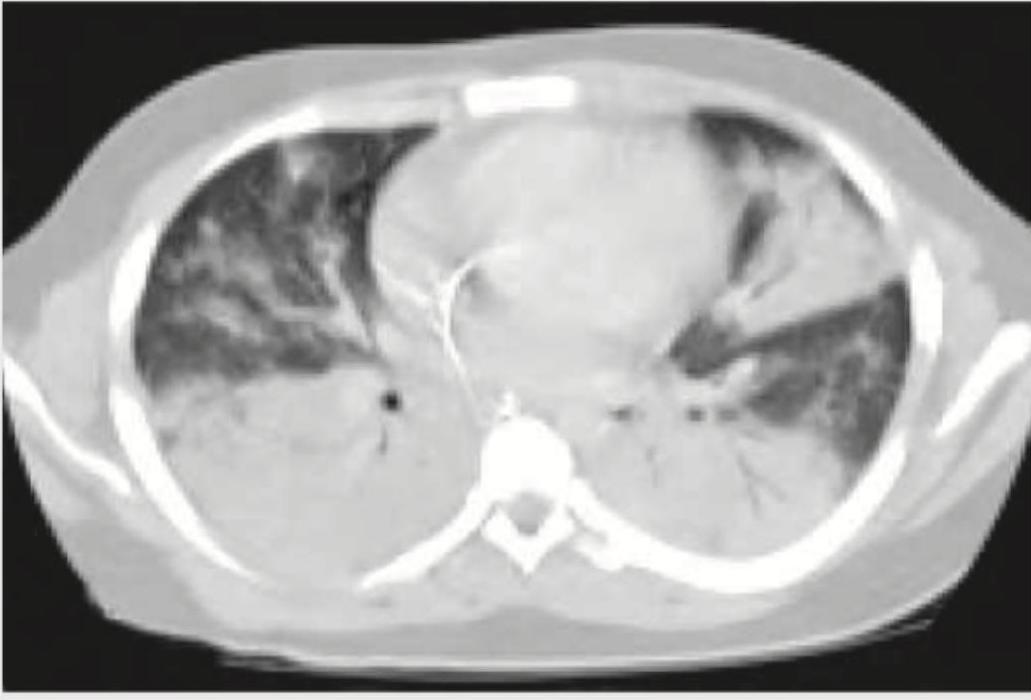

A cement slab fell on the chest of a 20-year-old construction worker. His condition deteriorated over the next 24 hours after admission. A repeat CT chest was performed. What does it show?

Explanation: ***ARDS*** - The CT image shows diffuse **bilateral ground-glass opacities** and consolidation, consistent with **acute severe inflammation** and fluid accumulation in the lungs. - The history of severe blunt chest trauma (a cement slab falling on the chest) with subsequent clinical deterioration over 24 hours is a classic presentation leading to ARDS. *Bronchiolitis obliterans organising pneumonia* - This condition typically presents with **patchy, migratory consolidations** or ground-glass opacities, often peribronchovascular, which is not the primary pattern seen here. - While it can be secondary to lung injury, the rapid onset and diffuse nature following severe trauma are more characteristic of ARDS. *Hemothorax* - A hemothorax would appear as a **fluid collection** (high attenuation due to blood density) in the pleural space, typically layering dependently, not as widespread parenchymal opacification. - While possible following trauma, the image shows lung parenchymal changes rather than isolated pleural fluid. *Cardiac tamponade* - Cardiac tamponade involves the **accumulation of fluid in the pericardial sac**, leading to external compression of the heart and impaired filling. - This would manifest as an enlarged cardiac silhouette with effacement of cardiac chambers and possibly distended vena cava on CT, but not the diffuse pulmonary infiltrates seen here.